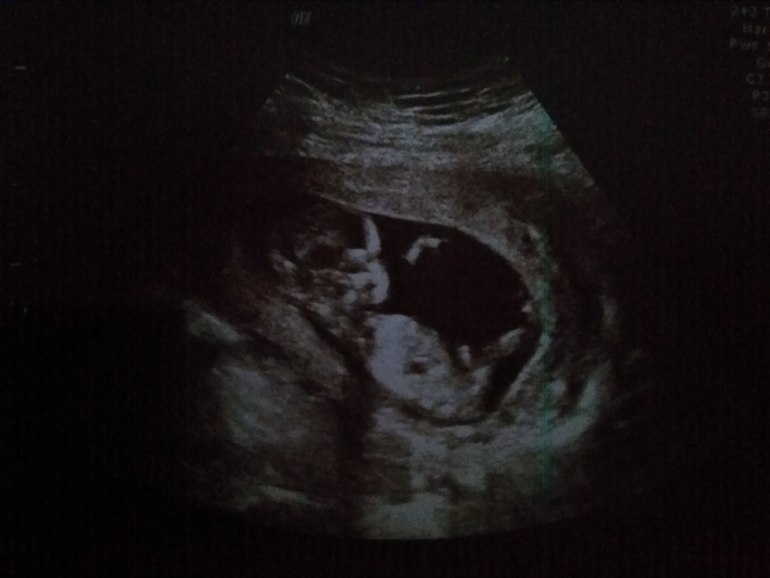

Ну, все! Выдохнула! Все хорошо! Ииииии... Не буду томить, у нас будет девочка! Теперь полный комплект!

Все у нас отлично! Но из-за того что плацента по передней стенке, плюс я не дюймовочка, сложно рассмотреть сердце. Но визуально все замечательно. ...